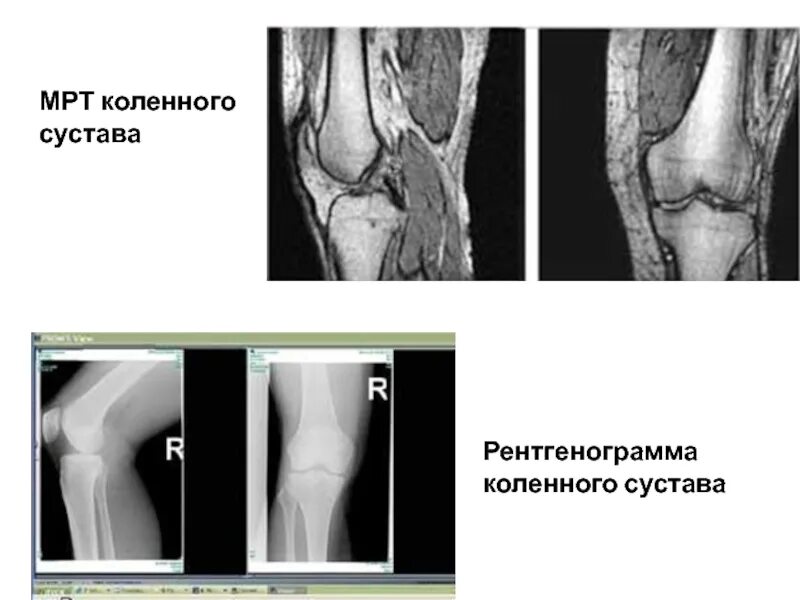

Мрт коленного сустава набережные